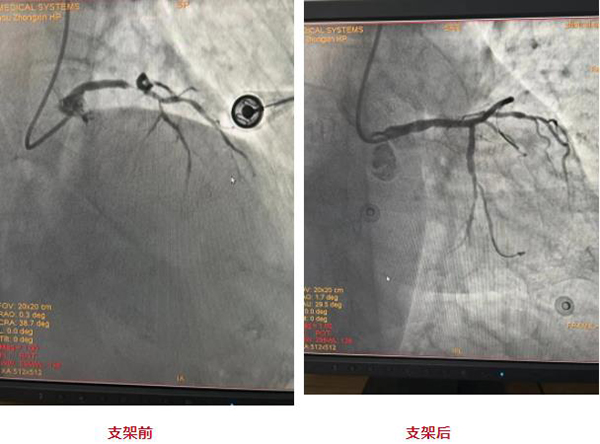

取得患者及家屬知情同意后,立即進(jìn)行術(shù)前準(zhǔn)備,行急診經(jīng)皮冠狀動(dòng)脈造影及PCI術(shù)?,F(xiàn)患者無(wú)胸悶氣短及心前區(qū)疼痛癥狀,正觀察治療中。

2023年2月11日19:20,49歲男性患者,以胸痛3小時(shí)余為主訴入急診科。患者于3小時(shí)前無(wú)明顯誘因出現(xiàn)胸痛,為胸骨后悶痛,無(wú)其他部位放散,伴氣短及大汗,可平臥,偶有頭暈,曾有惡心嘔吐,嘔吐物為胃內(nèi)容物,自行含服“速效救心丸”癥狀無(wú)明顯緩解,故于當(dāng)?shù)蒯t(yī)院就診,診斷為“急性下壁心肌梗死”,并給予急診藥物溶栓治療,后仍有胸痛,故為求進(jìn)一步診治來(lái)我院就診?;颊卟?lái)無(wú)發(fā)熱,無(wú)咳嗽咳痰,無(wú)意識(shí)不清,飲食及睡眠尚可,二便正常?;颊呒韧悄虿∈芳s7年(具體用藥不詳)、否認(rèn)高血壓及腦血管病病史。經(jīng)查體和輔助檢查診斷為:

1.冠狀動(dòng)脈粥樣硬化性心臟病 急性下壁心肌梗死 心功能KillipⅠ級(jí) 。

2.2型糖尿病。

經(jīng)患者及家屬知情同意和術(shù)前準(zhǔn)備后行急診經(jīng)皮冠狀動(dòng)脈造影及PCI術(shù)?,F(xiàn)患者無(wú)胸悶氣短及心前區(qū)疼痛癥狀,正觀察治療中。